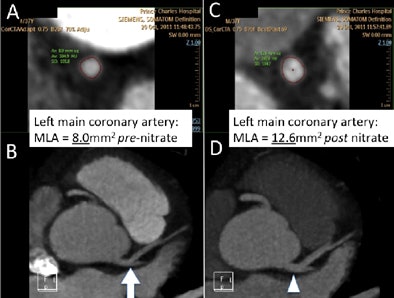

| A second contrast-enhanced acquisition (prospective ECG-triggered at 70% RR with no padding, b26f kernel with a reduced z-axis to cover the proximal coronary arteries, dose-length product [DLP] = 60) was performed nine minutes after two sprays of sublingual nitrate and additional 10 mg IV metoprolol to achieve a heart rate of 53 bpm. Contrast-phase timing is improved on the second acquisition (images above), with less contrast in the pulmonary circuit (332 HU versus 167 HU) and more contrast in the aorta and coronary arteries (365 HU versus 382 HU). Total DLP for all three acquisitions was 175 mGy/cm, for a total effective dose of 2.45 mSv. Of interest, the luminal diameter of the proximal LAD increased from 8.0 mm2 to 12.6 mm2 after sublingual nitrate (image below). The final images show eccentric, positively remodeled, calcified plaque in the LAD with mild (25% to 49%) sequential stenoses but no significant obstructive lesion (images above). Also of note, cardiac MR was performed on the same day to quantify left ventricular function, right ventricular function, and left ventricular mass due to history of hypertension, revealing a left ventricular ejection fraction of 57%, and left ventricular mass/index of 126 g/m2 indicating mild left ventricular hypertrophy. The patient's medical therapy was increased with the addition of ezetemibe to a potent statin, aiming for an LDL of < 1.5 mmol/L (< 58 mg/dL), and an ACE inhibitor added for hypertension and atherosclerosis control. This case illustrates the importance of heart rate control, sublingual nitrates, review of images at the time of acquisition, choosing the appropriate acquisition protocol to suit the patient heart rate and patient size. |